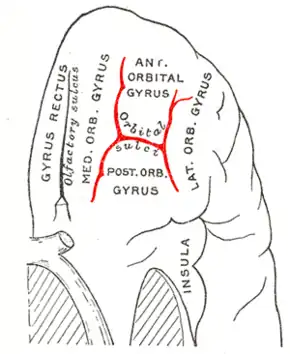

Orbital sulcus

| Orbital sulci | |

Orbital surface of left frontal lobe. | |

The inferior or orbital surface of the frontal lobe is concave, and rests on the orbital plate of the frontal bone. It is divided into four orbital gyri by a well-marked H-shaped sulcus the orbital sulcus.